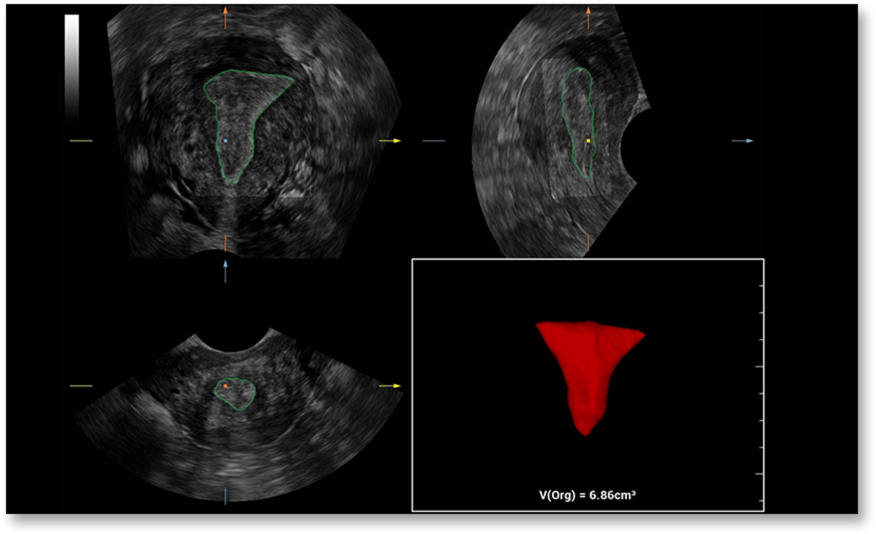

Smart FLC-ը ավտոմատ սահմանում է ֆոլիկուլների քանակը և հաշվարկում է դրանցից յուրաքանչյուրի ծավալը՝ ձվարանների եռաչափ պատկերի հիման վրա, ինչը ապահովում է ֆոլիկուլների ճշգրիտ գնահատում, որը անհրաժեշտ է արտամարմնային բեղմնավորման (ԷԿՕ) համար։